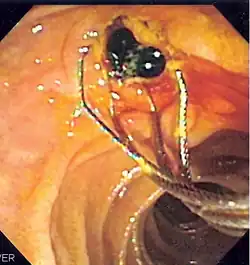

Duodenoscopic image of two black pigment stones extracted from common bile duct after sphincterotomy

When needed, the sphincters of the ampulla and bile ducts can be enlarged by a cut (sphincterotomy) with an electrified wire called a sphincterotome for access into either so that gallstones may be removed or other therapy performed.[10]